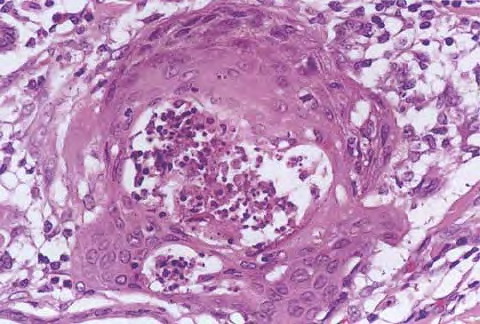

The histopathologic features of keratoacanthoma depend on the stage of evolution of the tumor. In early, proliferative lesions, the epithelium is markedly hyperplastic, and the central keratotic plug is not as pronounced as in fully developed lesions. The lesion has an overall symmetric aspect . Although atypical cells do not represent the majority of the cells in typical keratoacanthoma, there may be atypical keratinocytes and mitoses, especially at the lower margin of the tumor. Nests of epithelial cells may detach from the main tumor mass and be found in the superficial reticular dermis. Fully developed, mature lesions are characterized by a large central core of keratin surrounded by a well-differentiated proliferation of squamous epithelium that in some cases may resemble squamous cell carcinoma . The epidermis at both sides of the central core extends over the keratotic area in a fashion that has been described as “lipping” or “buttressing,” giving a distinct crateriform appearance to the lesion. Nests and strands of keratinocytes may be found apart from the main bulk of the tumor but usually do not extend lower than the level of sweat glands .

Cytomorphologically, large keratinocytes with eosinophilic cytoplasm are commonly observed, together with atypical cells and mitoses . An inflammatory infiltrate containing lymphocytes, plasma cells, histiocytes, eosinophils, and neutrophils is a common feature, and in some instances may be conspicuous. Neurotropism and even vascular invasion can be observed in otherwise typical keratoacanthomas, but the prognosis does not seem to be affected by these histopathologically worrisome features .